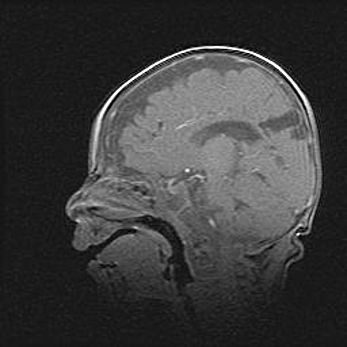

Мальформация Денди-Уокера. Киста задней черепной ямки.

Агенезия мозолистого тела.

Возраст: 2,5 месяца

Вес: 2420 г

Пол: женский

Окружность головы: 37 см

Срок гестации: 32 недели

Мальформация Денди—Уокера — редкий вид патологии ЦНС, представляющий собой врожденный порок развития каудального отдела ствола и червя мозжечка, ведущий к неполному раскрытию срединной (Мажанди) и латеральных (Лушка) апертур IV желудочка мозга. Для этогно синдрома характерна триада симптомов: гипотрофия червя мозжечка и/или полушарий мозжечка, кисты задней черепной ямки, гидроцефалия различной степени. В 70% случаев порок сочетается и с другими аномалиями головного мозга, в частности с агенезией мозолистого тела.